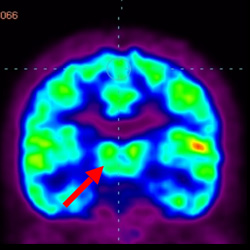

細(xì)胞治療前 PET CT 掃描顯示神經(jīng)組織中的藍(lán)/黑色區(qū)域,表明腦癱引起的大腦損傷。